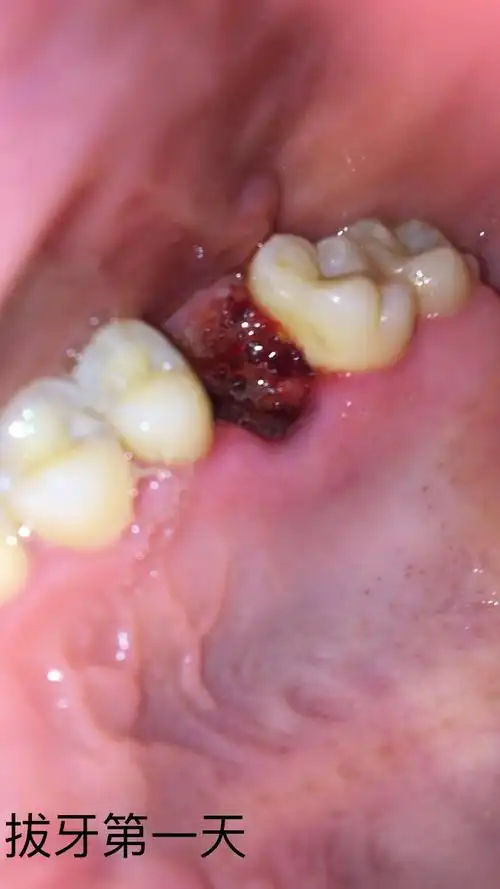

拔牙全程多图慎点恢复期全过程